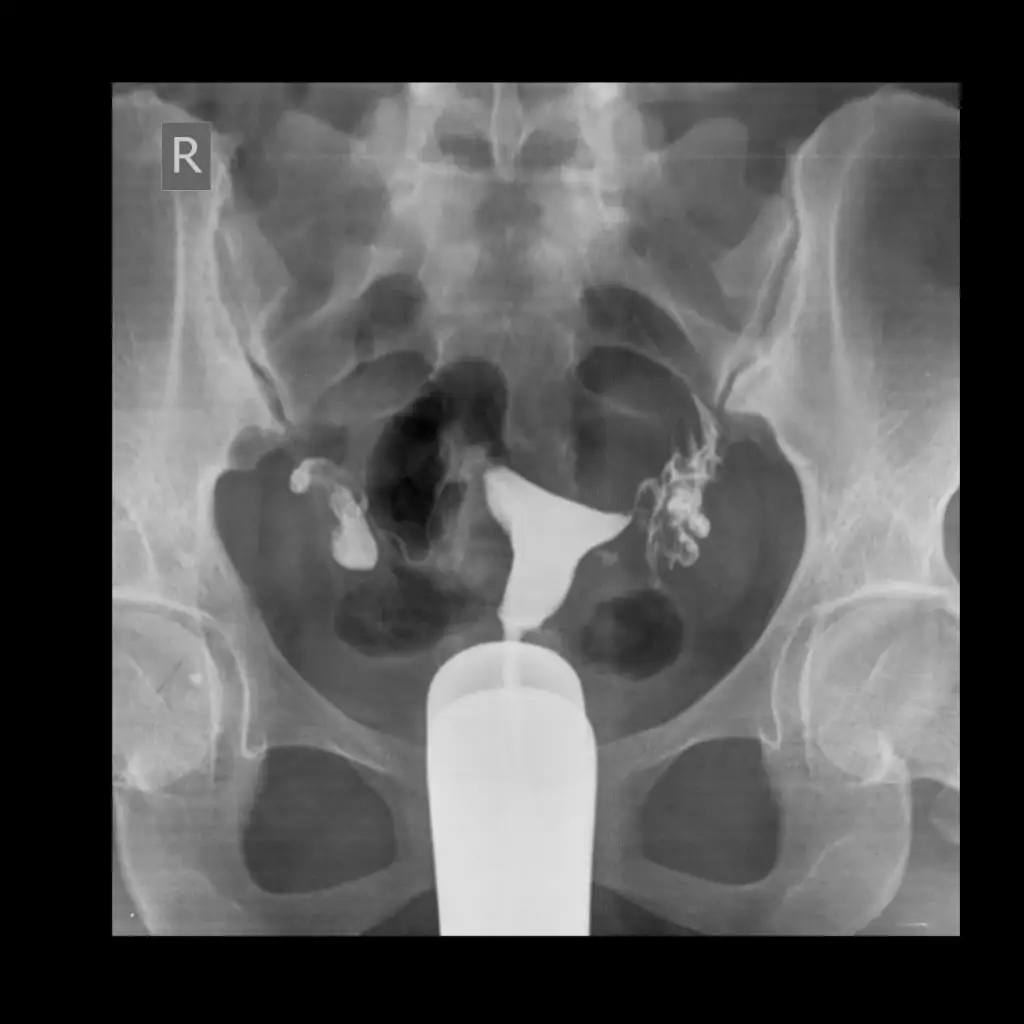

Dün rahim filmi çekildim resimleri ekliyorum arkadaslar anlayanlar varsa herhangi bir sorun görünüyor mu

Eklentiler

• IMG-20201215-WA0020.webp

15,7 KB · Görüntüleme: 55

• IMG-20201214-WA0001.webp

16,7 KB · Görüntüleme: 53